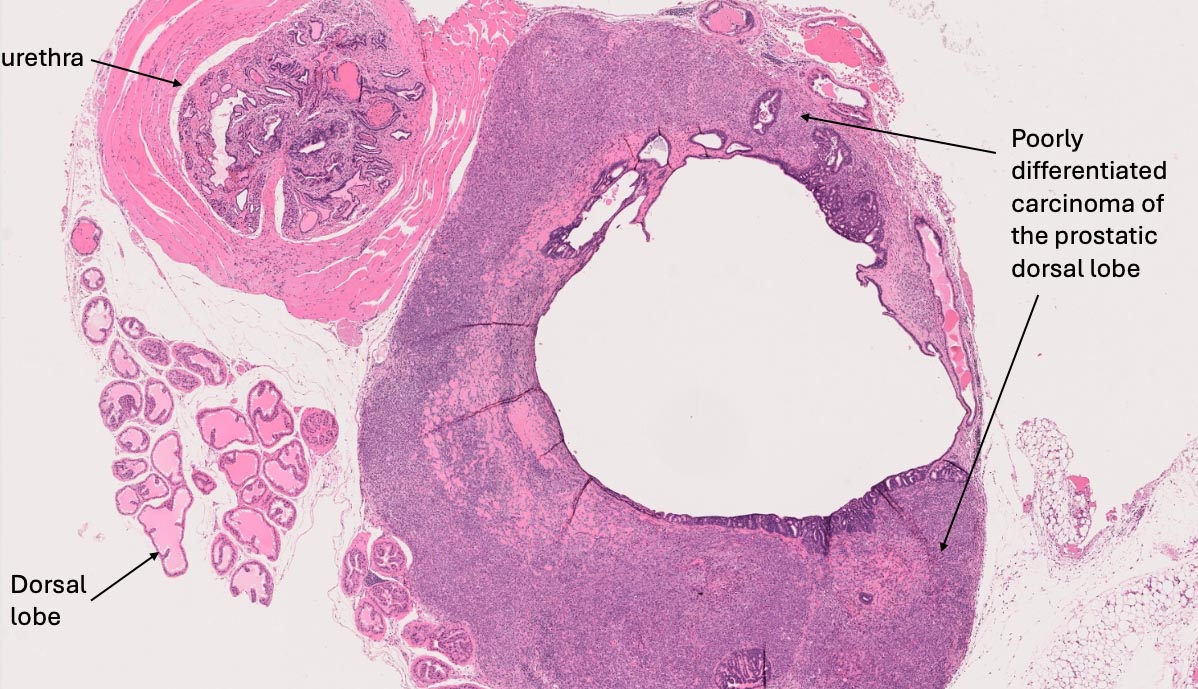

We have also explored the degree to which tumors found in male UM-HET3 mouse reproductive systems involve the prostate. Out of 95 such mice for which we have reproductive tissue samples, we identified only two animals (2.1%) with prostate tumors. One of these animals, found to have a poorly differentiated carcinoma in the prostate (Figure 5), also had tumors in four other locations. The other, diagnosed with a very early, very small carcinoma, had no other tumors.